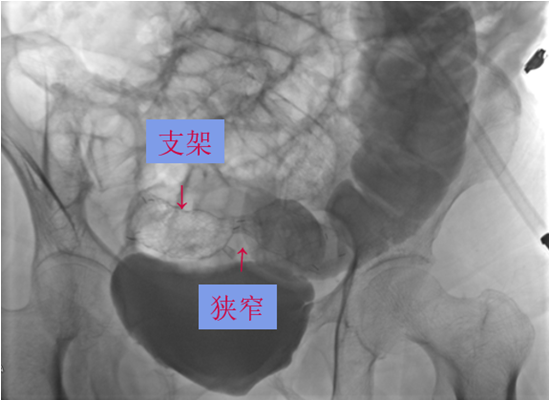

结直肠癌是我国常见的恶性肿瘤,患者就诊时多已为晚期或局部晚期。由于肿瘤瘤体巨大,侵犯邻近脏器,多个脏器受累,临床处理有一定困难。部分外科医生面对晚期结直肠癌时选择放弃手术。但事实上,多学科综合治疗能使晚期或局部晚期患者获得相对好的治疗结果,不应该轻易放弃合理的外科手术。对于肿瘤巨大但没有远处转移,有多脏器受累的患者,直接手术切除困难,可以考虑进行术前的辅助治疗。外科手术原则是在能够达到R0切除的基础上,尽量保留脏器的功能,进行合理的区域淋巴结清扫。

这老太太87岁,肠癌梗阻,病情较晚,在其他医院不敢做,准备放弃了,来我院经过处理后,微创手术解决问题。